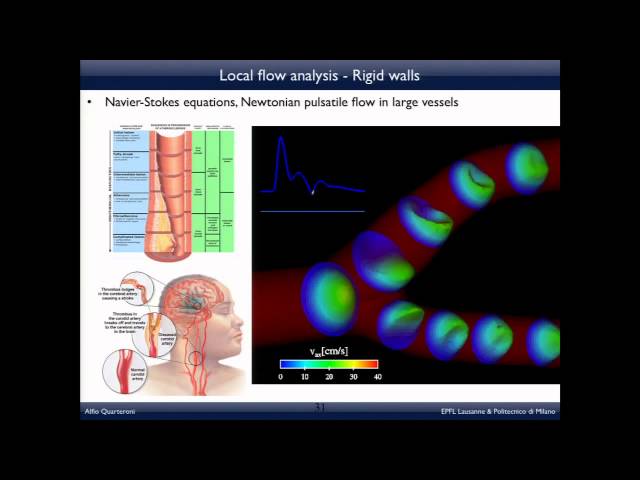

Conférence

Les mathématiques pour vivre mieux

Les mathématiques pour vivre mieux, une conférence données à l’invitation du département de mathématiques appliquées par Alfio Quarteroni, Professeur...